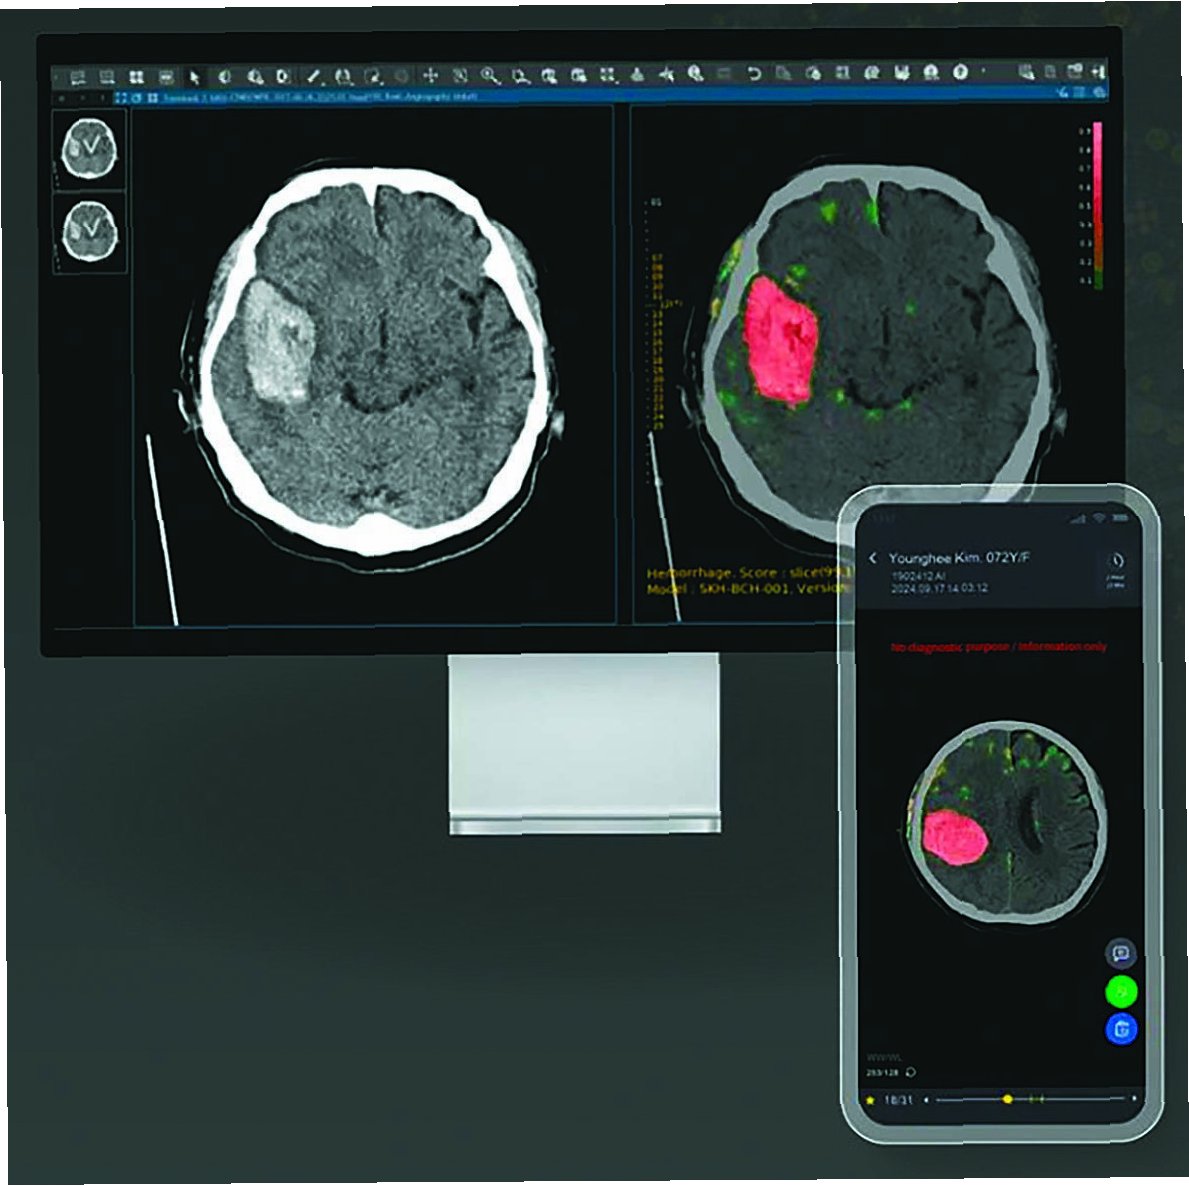

실제 의료 현장에서 AI 기반 뇌졸중 솔루션의 활용 사례가 증가하고 있습니다. AI는 응급실에서 뇌졸중 의심 환자의 CT 영상을 분석하여 뇌출혈 여부를 빠르게 판단하고, 의료진에게 신속한 치료 결정을 돕습니다. AI는 뇌졸중 환자의 재활 치료 과정을 모니터링하고, 환자의 회복 속도에 맞춰 맞춤형 재활 프로그램을 제공합니다. AI 기반의 원격 의료 시스템은 뇌졸중 환자가 거주지에서 전문적인 의료 서비스를 받을 수 있도록 지원합니다. AI 기술은 의료진의 업무 부담을 줄이고, 환자 중심의 의료 서비스를 제공하는 데 기여합니다. AI 솔루션은 의료 자원이 부족한 지역에서도 뇌졸중 환자에게 효과적인 치료를 제공할 수 있도록 돕습니다.